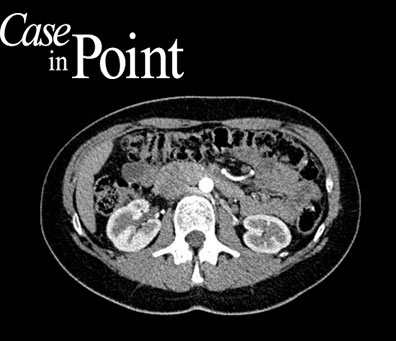

Case in Point  gives you the opportunity each weekday to work through a subspecialty case developed by a community of residents, their mentors, and expert subspecialty editors. Determine the differential diagnosis, make conclusions, review images, and solidify your knowledge of both unique and important diagnoses. Plus, eligible ACR physician members can earn free CME. Sign up to receive new cases delivered straight to your inbox every weekday. Nonmembers can also complete cases and claim CME.